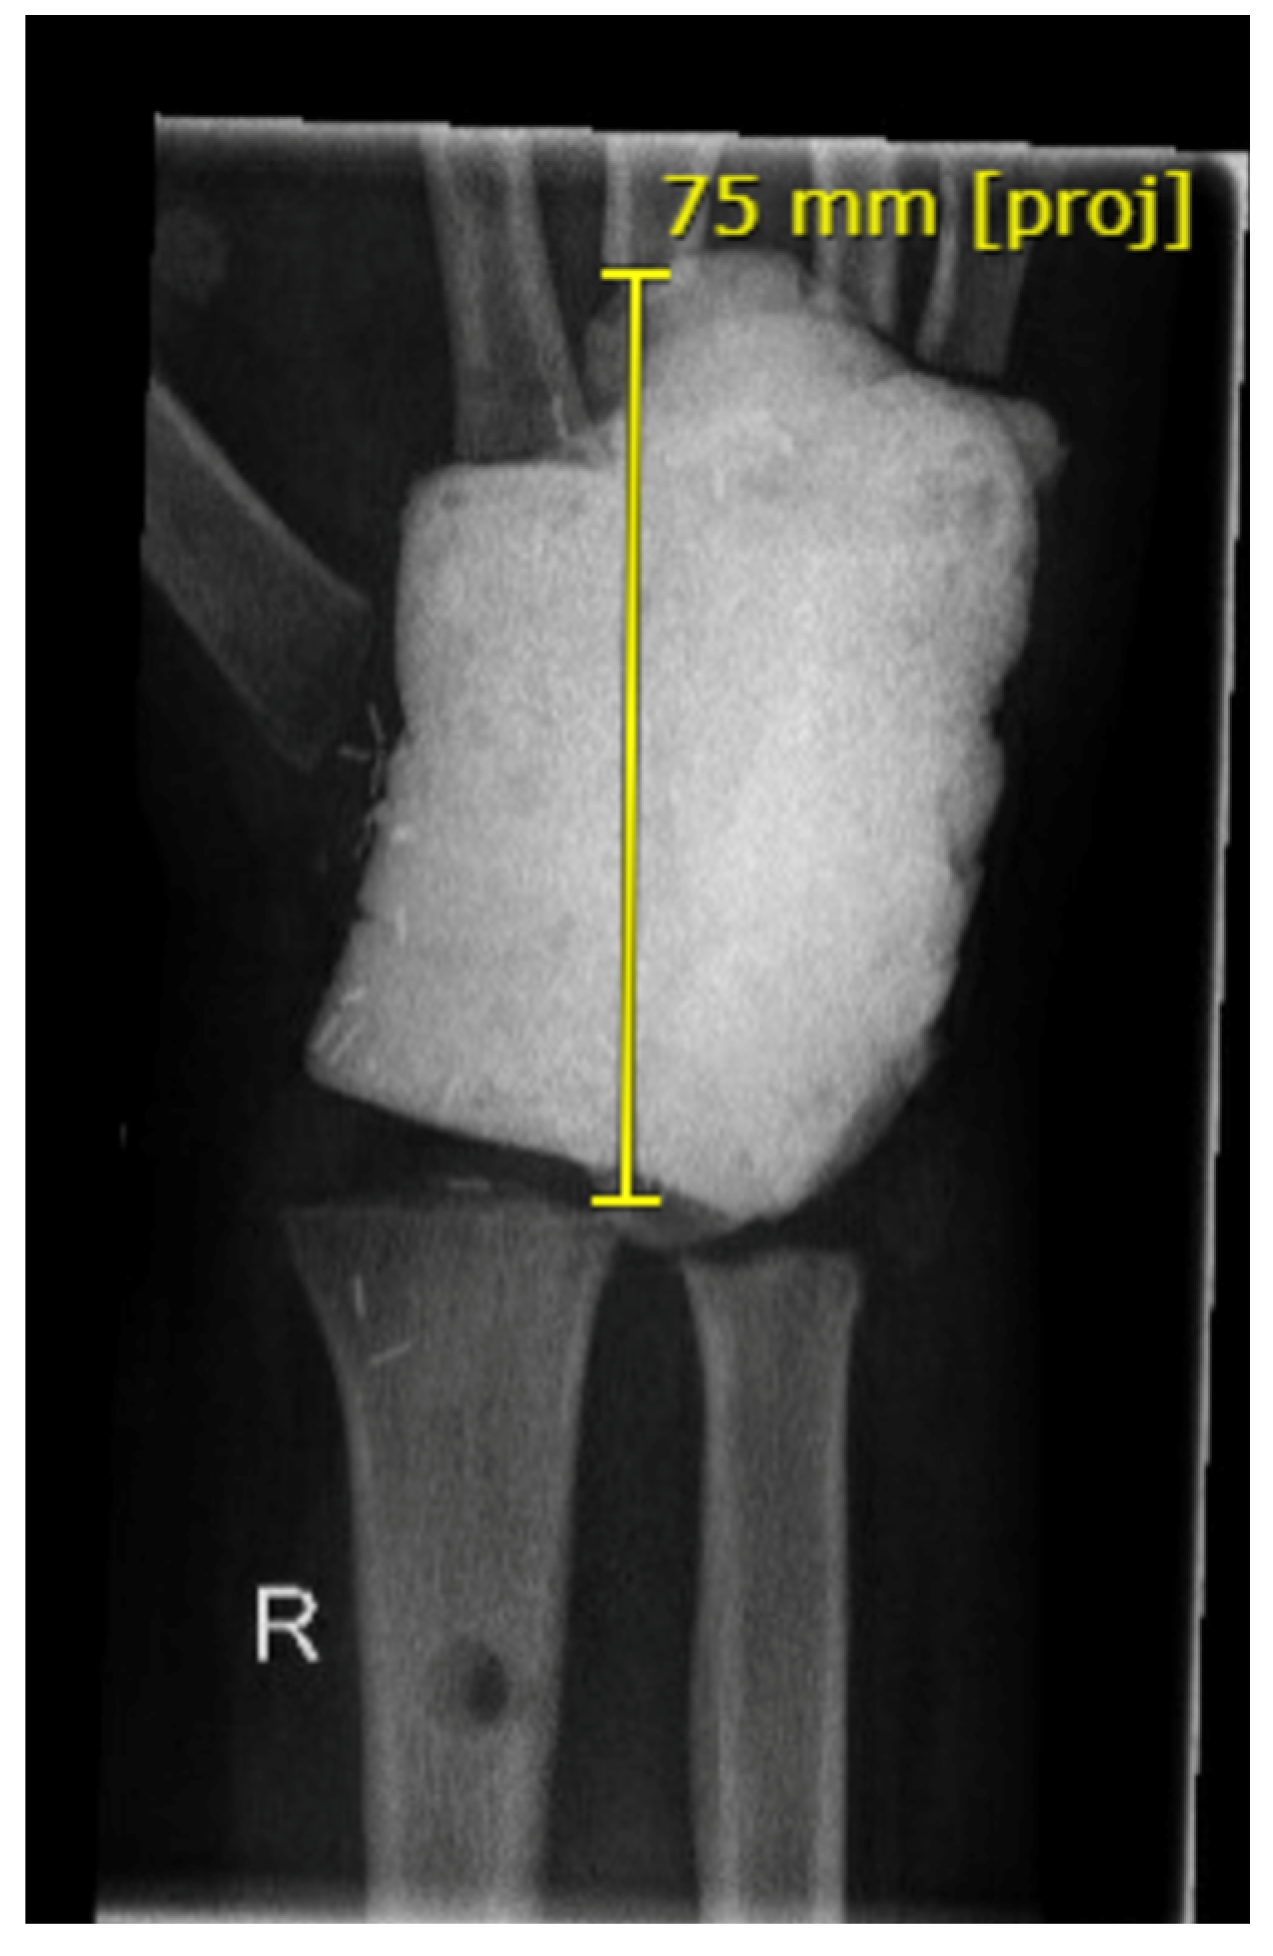

3.3. Group 3: Arthroplasty of the Proximal Wrist

| GROUP 3 | Case 4 | Distal radius involving the radiocarpal surface | Giant cell tumor | 14 | 41 | 8 cm | Vascularized fibula | Wrist arthroplasty | 60-0-50° N/A | 30-0-40° 80-0-70° | 65% | MMWS = 70 DASH = 17 | yes |